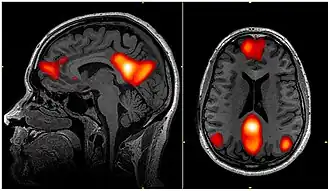

La red neuronal por defecto (RND) es un conjunto de regiones del cerebro que colaboran entre sí y que podría ser responsable de gran parte de la actividad desarrollada mientras la mente está en reposo.

Tras conocerse la posibilidad de una vida interna del cerebro, a mediados de los noventa se descubrió que cuando los sujetos realizan alguna tarea, ciertas regiones del cerebro experimentaban una disminución de su nivel de actividad, si se compara con el estado basal de reposo. Tales áreas (una parte de la corteza parietal medial y la corteza prefrontal medial), consideradas las «centralitas principales» de la RND, experimentan esa caída cuando otras áreas se ven implicadas en la ejecución de una tarea determinada.